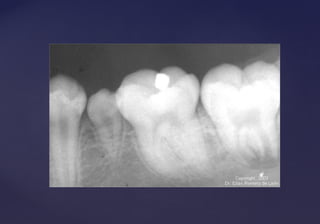

Perlas adamantinas

“Nodulos” “Gotas” “Formaciones” “Esferas”

 SonSon pequeñas áreas de esmalte que se aponen sobre la dentina de la raíz,

cuando lo normal es que sobre la dentina de la raíz haya siempre

cemento.

 La vaina epitelial de Hertwig permanece unida a la dentina subyacente enLa vaina epitelial de Hertwig permanece unida a la dentina subyacente en

la zona cervical, el epitelio elabora tejido del esmalte dando comola zona cervical, el epitelio elabora tejido del esmalte dando como

resultado un nódulo o perla.resultado un nódulo o perla.

 Se localizan en las raíces de los molares inferiores.Se localizan en las raíces de los molares inferiores.

 Particularmente en la zona de furcación.Particularmente en la zona de furcación.

 A veces unidas a la corona por una línea o banda de esmalte.A veces unidas a la corona por una línea o banda de esmalte.

 Rx: RADIOPACORx: RADIOPACO